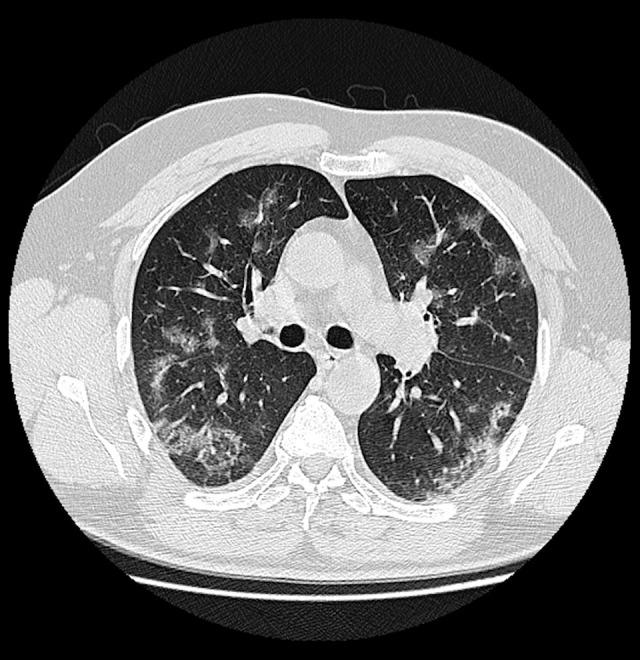

BACKGROUND Chest imaging may be taken into consideration in detecting viral lung infections, especially if there are no tests available or there is a need for a prompt diagnosis. Imaging modalities enable evaluation of the character and extent of pulmonary lesions and monitoring of the disease course. The aim of this study was to verify the prognostic value of chest CT in COVID-19 patients. MATERIAL AND METHODS We conducted a retrospective review of clinical data and CT scans of 156 patients with SARS-CoV-2 infection confirmed by real-time reverse-transcription polymerase-chain-reaction (rRT-PCR) assay hospitalized in the Central Clinical Hospital of the Ministry of the Interior in Warsaw and in the Medical Centre in Łańcut, Poland. The total severity score (TSS) was used to quantify the extent of lung opacification in CT scans. RESULTS The dominant pattern in discharged patients was ground-glass opacities, whereas in the non-survivors, the dominant pulmonary changes were consolidations. The non-survivors were more likely to have pleural effusion, pleural thickening, lymphadenopathy, air bronchogram, and bronchiolectasis. There were no statistically significant differences among the 3 analyzed groups (non-survivors, discharged patients, and patients who underwent prolonged hospitalization) in the presence of fibrotic lesions, segmental or subsegmental pulmonary vessel enlargement, subpleural lines, air bubble sign, and halo sign. CONCLUSIONS Lung CT is a diagnostic tool with prognostic utility in COVID-19 patients. The correlation of the available clinical data with semi-quantitative radiological features enables evaluation of disease severity. The occurrence of specific radiomics shows a positive correlation with prognosis.

出院患者的主要表现为磨玻璃影,而未存活患者的主要肺部改变为实变。未存活患者更有可能出现胸腔积液、胸膜增厚、淋巴结病、空气支气管征和支气管扩张。在 3 个分析组(未存活患者、出院患者和住院时间延长的患者)中,纤维化病变、肺段或亚段血管扩大、胸膜下线、气液征和晕征的存在无统计学差异。